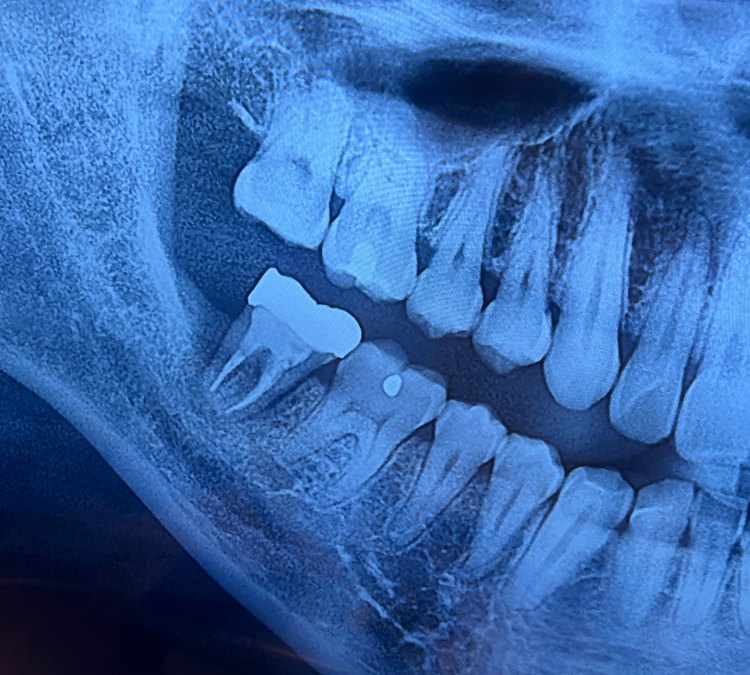

오랜만에 찾은 치과는 정말 낯설었습니다. 이전에 어렵게 살려서 이 모양으로 씌어 놓은 크라운 속에 염증이 차서 잇몸이 녹고 있으며 이를 뽑아야하는 지경에 이르렀다는 것입니다.

신경치료 할때 너무 힘들고 고통스러웠기 때문에 겁부터 났습니다. 엑스레이는 멀쩡해 보이는데 수술하지 말까?